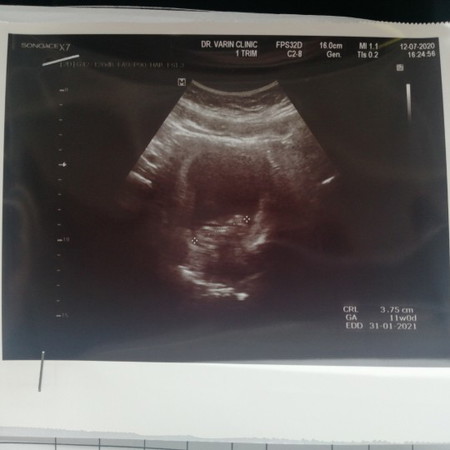

11 วีค

ท้องได้ 11 วีคค่ะ ไปซาวด์มาน้องยาวประมาน 3.75 ถือว่าปกติ หรือ น้องตัวเล็กไปไหมค่ะ